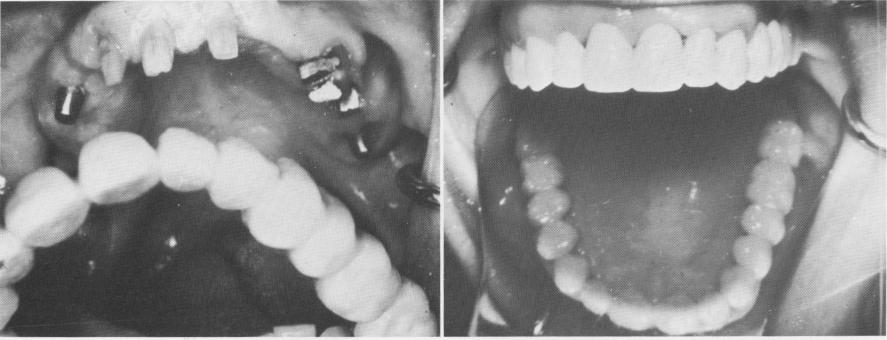

Fig. 11-79. After all the implants were seated, the tissues were sutured closed. Soldered gold copings attached to the required number of pontics are fitted over the prepared teeth.

Fig. 11-80. The aluminum shells trimmed and placed over the implant posts with soft compound.